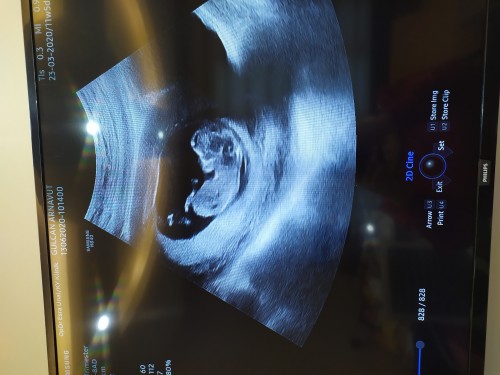

11+5 günlük bebeğimin doktorumuz cinsiyetini net göremediği için bişey söylemek istemedi şu an. Sizde nedir ♥️♥️♥️

Nub teosrisi e göre kızce bu minik ❤️

İşin şakası tabi bu erkekse olabilir ama en net 16 da belli olur azdaha sabret kuzum